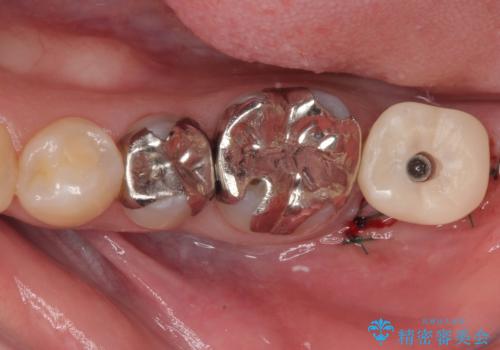

- 奥歯を抜歯してから放置しているとのことで来院された患者様です。

歯が割れて抜歯になってしまったとのことで、咬合力に抵抗できるよう、インプラントによる補綴治療を行うこととしました。

長い期間歯が欠損していた下顎奥歯に、インプラント埋入と同時に仮歯を装着すると(埋入即時荷重インプラントを行うと)、舌の付け根で仮歯を横向きに押してしまい、インプラントが脱落する危険性が高くなります。

インプラント埋入時に、装着できる状態の仮歯を用意するものの、埋入後すぐには加重させず、インプラントが無事に生着したことを確認した後に装着することで、危険を回避しつつ外科処置や痛みの少ないスムーズな治療を行うことができます。